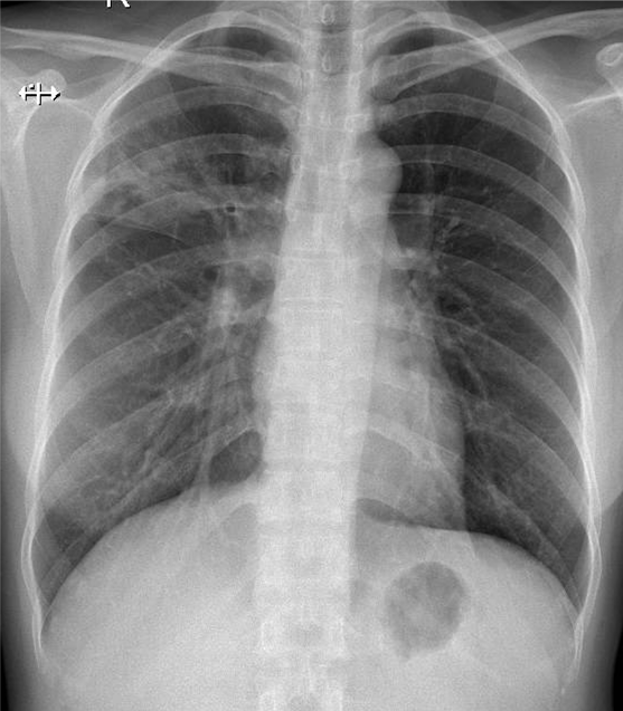

1-Thâm nhiểm phế nang thùy trên phổi (P) => Viêm phổi